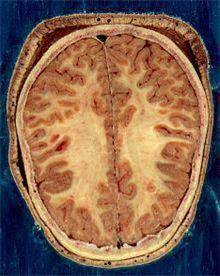

![뇌의 백질과 회색질 [출처: 위키백과]](https://img1.daumcdn.net/thumb/R658x0.q70/?fname=https://t1.daumcdn.net/news/202211/29/yonhap/20221129103538680fbcq.jpg)

뇌는 신경 세포체로 구성된 겉 부분인 대뇌 피질과 신경 세포들을 서로 연결하는 신경 섬유망이 깔린 속 부분인 수질로 이루어져 있다. 피질은 회색을 띠고 있어 회색질, 수질은 하얀색을 띠고 있어 백질이라고 불린다.